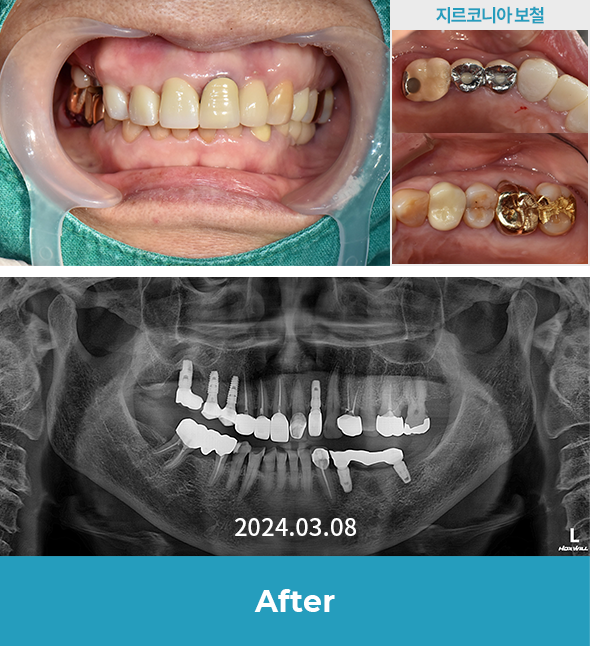

· (임플+지르) 기존 보철물 뜯어내고 임플란트 + 일부 신경치료 후 지르코니아 보철물 진행 case

치료 후 사진은

자세히보기에서 확인하실 수 있습니다.

+ 자세히보기